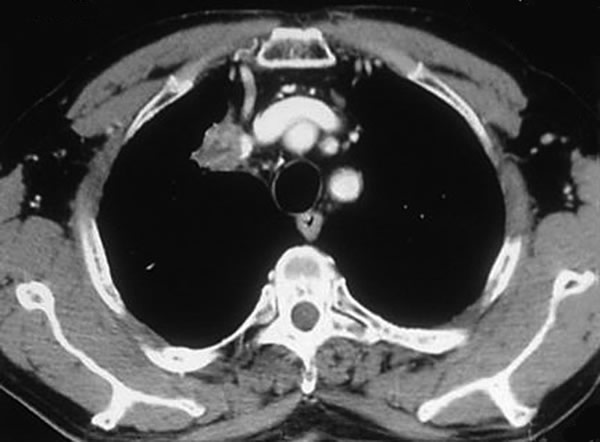

The subclavian artery can usually be dissected through the subadventitial plane (Video 8). Local branches (e.g., the internal mammary artery, thyrocervical trunk, or occasionally the vertebral artery) should be identified and transected if necessary. If the subclavian artery is invaded by tumor (Figure 10), the involved segment can also be resected and reconstructed through a posterior approach (Figure 11). After systemic heparinization, the artery is cross-clamped proximally and distally excluding the invaded segment and revascularized using either an end-to-end anastomosis or, more commonly, the interposition of a polytetrafluoroethylene (PTFE) graft, 6 to 8 mm in diameter (Video 9).

| Figure 10. Chest CT-scan shows the invasion of the subclavian artery by Pancoast tumor. | Figure 11. The invaded artery was resected and replaced by a PTFE graft through a posterior approach. |